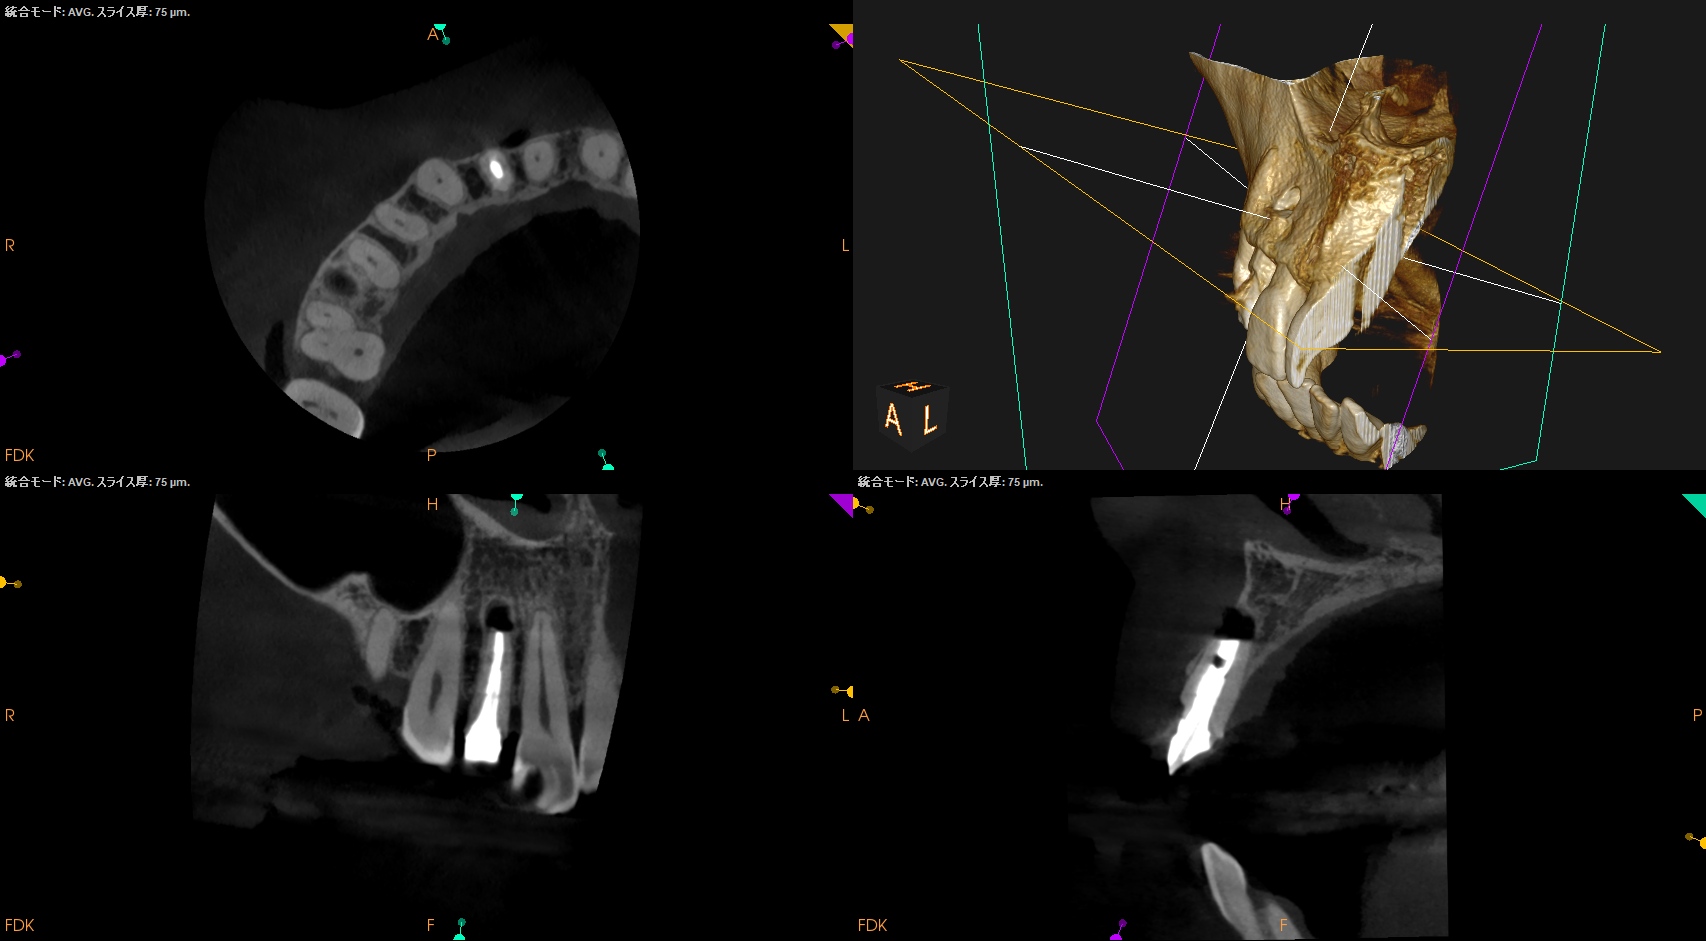

根尖が既に開いており、圧痛があったことから治療は再根管治療ではなく、歯根端切除術であるということがわかる。

クラウンのマージンより11.5mm下方に#7のApexはあり、そこを3mm切断するには頬舌的に4.4mmの幅があるということがわかる。

実にEasyなApicoectomyだ。

Recommended Tx: Core build up w Fiber Post⇨Apicoectomy

術後にPA, CBCTを撮影した。

気泡が逆根管充填材に混入したが、問題はないだろう。